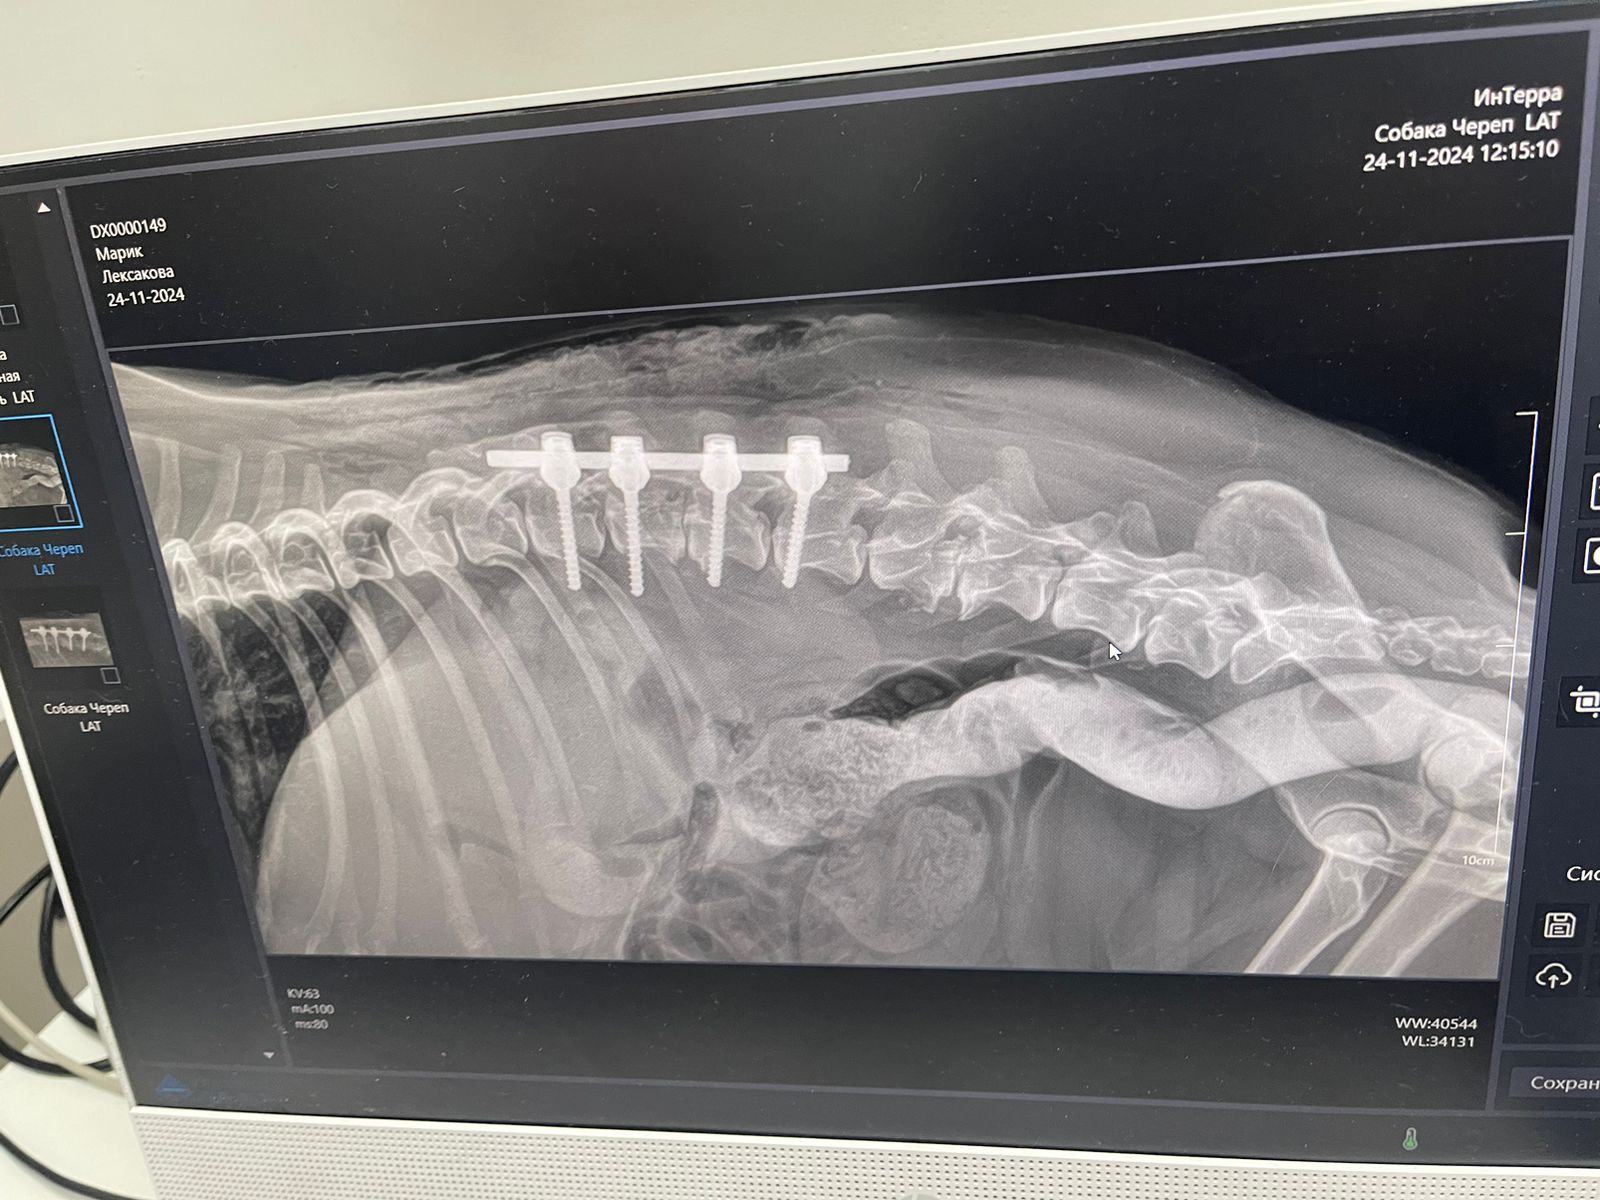

Марику сделали операцию. Один позвонок у него был развалившийся, второй что-то куда-то выдавливал. Но все не так плохо, мозг живой, чувствительность в лапах сохранилась на момент операции. Поставили стабилизатор позвоночника и что-то еще делали.

Чеки на сегодня. Скидку 15 процентов сделали.

Поговорила с врачом, сфоткала рентген с экрана компьютера.